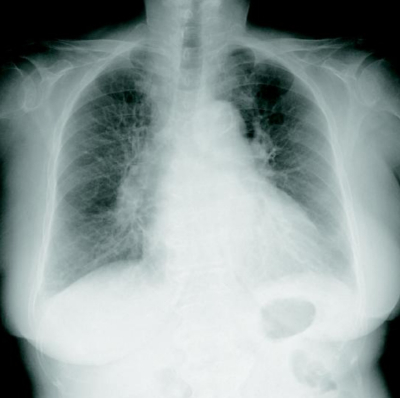

検査所見 : 尿所見:蛋白:(-)、糖:(-)、ケトン体:(-)、潜血:(-)。血液所見:赤血球 444 万、Hb 13.5 g/dL、Ht 41 %、白血球 6,900(好中球 65 %、好酸球2%、好塩基球0%、単球4%、リンパ球 29 %)、血小板 22 万。血液生化学所見:総ビリルビン 0.5 mg/dL、AST 21 U/L、ALT 18 U/L、LD 175 U/L(基準 120〜245)、ALP 166 U/L(基準 115〜359)、γ-GTP 35 U/L(基準8〜50)、CK 121 U/L、尿素窒素 20 mg/dL、クレアチニン 0.7 mg/dL、血糖 103 mg/dL、Na 142 mEq/L、K 3.9 mEq/L、Cl 101 mEq/L。脳性ナトリウム利尿ペプチド(BNP)2,200 pg/mL(基準 18.4 以下)。心電図及び胸部エックス線写真を別に示す。